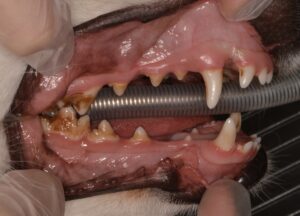

術前の写真です↓

奥歯を中心に歯石の付着がみられます。また、全体的に歯と歯肉の境界が赤く腫れてきている箇所も見られ、この部分には歯肉炎が起きていることが予想されます。

歯肉炎とは、歯周病の初期段階であり口の中の細菌に反応して歯肉が炎症を起こしている状態です。進行すると歯を支える組織が壊されていき(歯周炎)歯がぐらついたり顎の骨の骨折に繋がることすらあります。

歯肉炎が起こっている部分には表面だけでなく歯と歯肉の間の溝にも細菌の塊である歯垢や歯石が蓄積してきている状態ですので、この部分もきれいにする治療が必要です。わんちゃんの場合、歯肉の下や歯の裏側など、普段の歯磨きではどうしても磨ききれない場所が出てきてしまいますので、歯周病を進行させないためには定期的な麻酔下での処置が必要です。